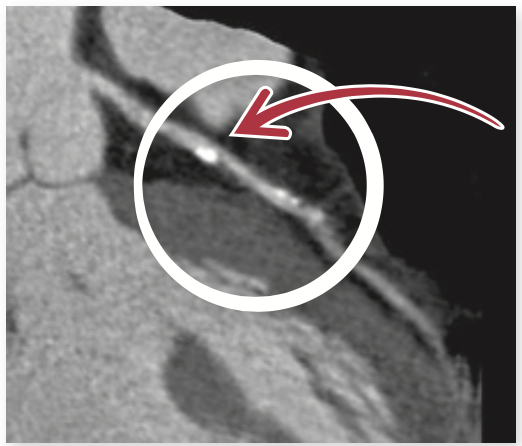

Coronary computed tomagraphy (CT) calcium scoring is a test used to determine whether an individual with no symptoms of coronary artery disease (CAD) has areas of calcified plaque in their coronary arteries.